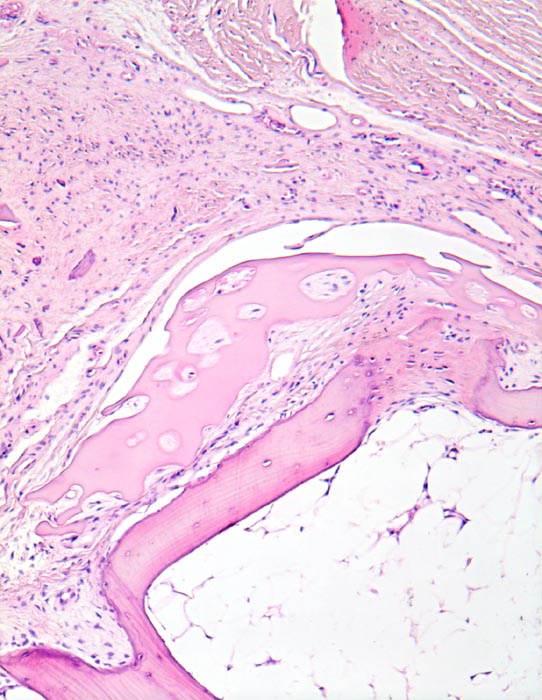

Rheumatoide Arthritis: Pannus

Überrest des hyalinen Gelenkknorpels. Der angrenzende Gelenkspalt wird ausgefüllt von bindegewebigem Pannus mit geringem Entzündungsinfiltrat. Auch zwischen Knorpel und Knochen findet sich Pannusgewebe. Das Pannusgewebe enthält abgesprengte Knochen- und Knorpelfragmente.

Als bedeutendster Faktor für die Knorpel- und Knochenzerstörung wird das Pannusgewebe angesehen, das sich von den synovialen Insertionen auf die Gelenkoberfläche erstreckt und sich unter Destruktion des kortikalen Knochens in den subchondralen Markraum eindrigt und hier mit Osteoklasten den Knochen abbaut. Für die Zerstörung des Gelenkknorpels sind somit der Oberflächen- und der Markpannus verantwortlich. In floriden Phasen finden sich an der Pannus-Knorpelgrenze neutrophile Granulozyten und Makrophagen, deren lytische Enzyme den Knorpel abbauen. Im Bild ist eine ausgebrannte Phase mit weitgehender Zerstörung der Gelenkfläche und minimalem Entzündungsinfiltrat.